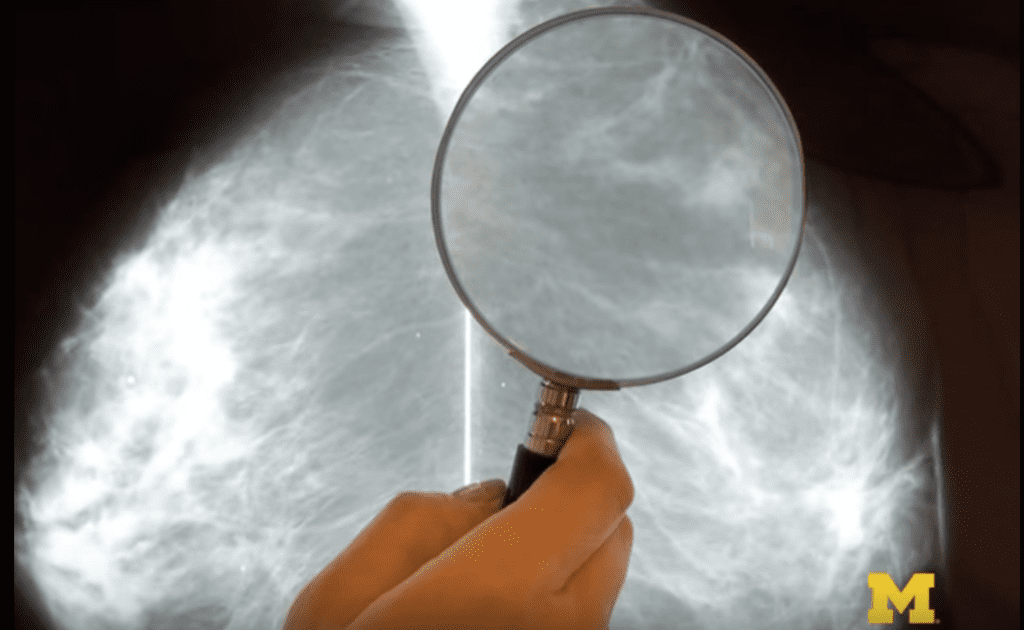

Student Spotlight: Mai Le – Finding a better way to diagnose breast cancer with MRI

The research group is using statistical signal processing to create crisper images with only 20% of the data required by a traditional MRI scan.